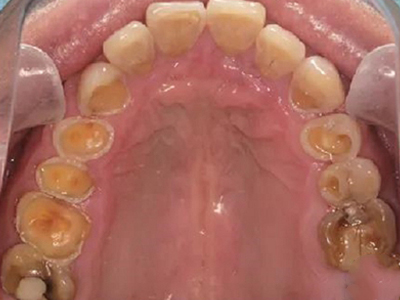

酸蚀症后排牙齿大量缺损图

酸蚀症患者的后排牙齿可发生大量缺损,一侧牙齿遗留圆盘状牙根,形似被切割,另一侧牙齿有大量凹陷坑洞,部分牙齿颜色发黑或呈黄褐色,其发生与长期接触酸性物质有关。